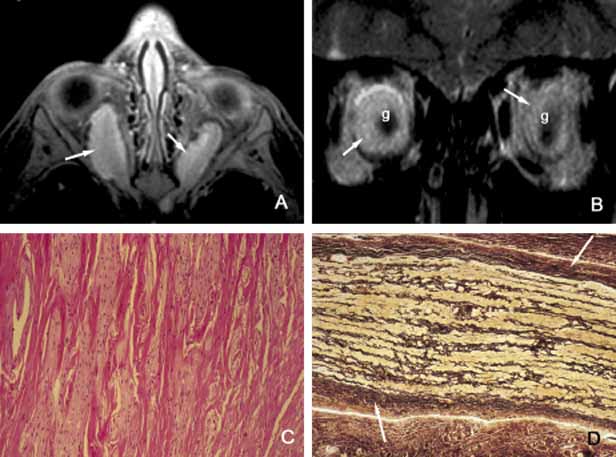

Graves Disease

Thyroid-associated orbitopathy, better known as Graves disease (Gd), is an idiopathic orbital inflammation that primarily involves the muscles and soft tissues of the orbit and the eyelids. The commonly involved muscles include inferior, medial, superior and lateral recti that cause swelling of the tissue leading to proptosis and eyelid retraction (Fig. 9). Gd is the most common cause of unilateral and bilateral proptosis in adults; although uncommonly it may be seen in children as well.

Fig. 9 Graves disease. Clinical findings of Graves disease are depicted in frame A, including bilateral proptosis and lid lag with extraocular motility disturbance, chemosis with prolapse of lacrimal gland and congestion of conjunctival and episcleral blood vessels. Axial CT scan (B) reveals marked swelling of all recti muscles. The histopathologic appearance of the extraocular muscle from a patient with Graves disease reveals chronic inflammatory infiltrates, primarily composed of lymphocytes and plasma cells (C). The extraocular muscle volume is increased because of diffuse endomysial fibrosis, mucopolysacccharide deposition and chronic inflammatory cell infiltration (D). The orbital fat, meninges and the optic nerve (blue arrow), large blood vessels of the orbit, such as ophthalmic artery and its branches (green arrows) and the ciliary ganglion (red arrow) do not show any inflammation. The enlargement of the extraocular muscles are well depicted in frame E, which represents a transverse section, approximately at the level indicated by the yellow line in frame B. (LR: lateral rectus; SR + L: superior rectus and levator complex; SO: superior oblique; MR: medial rectus; IR: inferior rectus; IO: inferior oblique). (Frames C, D, and E are the courtesy of Ralph C. Eagle, MD of Philadelphia, PA)

The pathogenesis of Gd is not completely understood; therefore, it is labeled as an “autoimmune” process.82,98 It has been suggested that individuals with HLA-B8 major histocompatility antigen Haplotype are genetically susceptible to Gd.99 The hypothesis is that circulating T-cells directed against an antigen in thyroid follicular cells recognize a similar antigen in extraocular muscles and orbital soft tissues.100 Experimental studies suggest that thyrotropin receptor (TSH-R) is one of the possible entities to stimulate the autoantibodies that lead to the inflammatory changes within orbital soft tissues. In Gd there is a predominance of T-cells with Th1 profile, although Th2 profile of cytokine production has also been reported.100 The cytokines stimulate fibroblasts to produce glycosaminoglycans that in turn lead to deposition of this substance within the muscle tissue leading to anatomic and functional deficiencies (Fig. 9). Although cell mediated immune reaction predominate in early Gd, humoral immunity plays a greater role in later phases.101

Some of the immune changes are reflected in the histopathology of Gd, which can basically be divided in two stages. The active inflammatory stage consists of perivascular edema and clustering of lymphocytes and plasma cells; lymphoid follicles are not frequent in Gd. In the chronic stage the volume of the involved orbital tissues are increased because of the deposition of glycoproteins and mucopolysaccharides and secondary to the infiltration of fibroblasts producing collagen. Later in chronic stages of the disease, the edema decreases and the muscles are primarily infiltrated with interstitial fibroblasts and chronic inflammatory cells leading to fibrosis.

Although 80% of patients with Gd present with a history of hyperthyroidism, approximately 10% suffer hypothyroidism or autoimmune thyroiditis; occasionally, an euthyhroid individual may also develop the signs and symptoms of Gd.102 Upper lid retraction is the most frequent clinical sign in early Gd (75%) followed by asymmetrical bilateral proptosis (60%) and restriction of extraocular muscles (40%). Compressive optic neuropathy may result secondary to the enlargement of the extraocular muscles in the apex. Optic nerve malfunction is manifested by afferent pupillary defects and color vision and visual field deficiencies in approximately 5% of Gd patients.

The best means of evaluation of extraocular muscles is imaging with CT and/or MRI.11 Axial CT scan is very valuable to depict the enlargement of the extraocular muscles and determine whether there is any infiltration into other orbital soft tissues. Coronal sections are also very useful to evaluate the enlargement of the muscles and their relationship to the optic nerve in the orbital apex.103 In differential diagnosis of Gd, one should keep in mind that it is not only the most frequent cause of bilateral proptosis but unilateral proptosis as well. Therefore, the slowly progressive unilateral presentation may be confused with orbital pseudotumors, neoplasia, and solitary vascular lesions such as orbital varix.104,105 Orbital metastatic neoplasms may also be confusing if they are limited to the extraocular muscles. Imaging usually reveals nodular enlargement of the muscle and the diagnosis of a metastatic disease may be confirmed with fine needle aspiration biopsy (FNAB). The treatment of Gd includes oral and intravenous steroids, radiation and surgery.